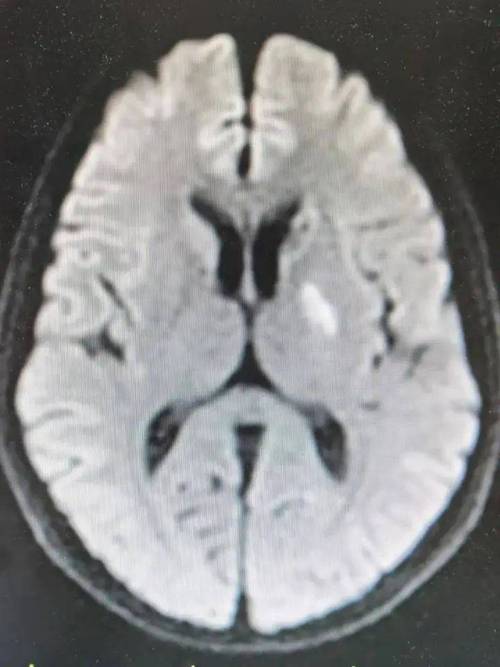

- 病灶形态:梗塞区域在CT上通常会表现为一个低密度(比周围正常的脑组织颜色要深/黑)的区域。

- 边界清晰:随着时间的推移(几周后),这个低密度区域的边界会变得非常清晰锐利,周围没有明显的水肿(这是急性期的主要表现)。

- 脑萎缩改变:长期来看,这个梗塞区域会导致局部脑组织体积缩小,可能伴有周围脑室的轻微扩大。